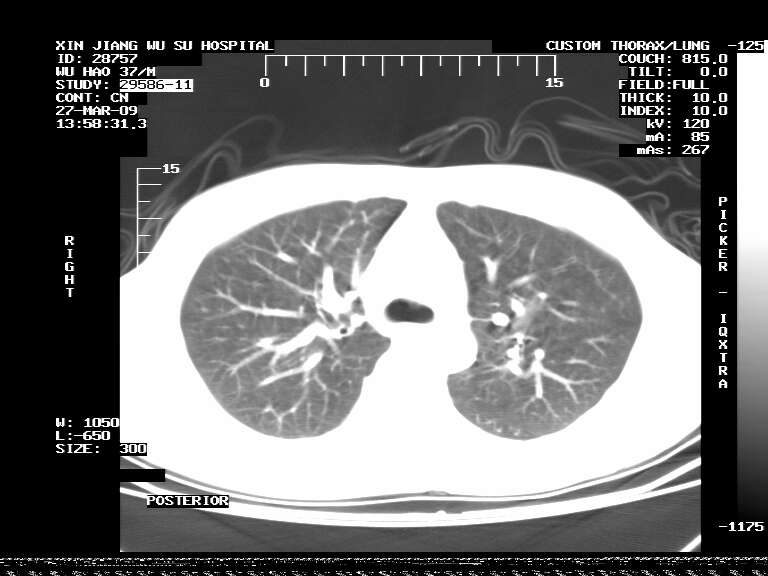

男,37岁,体检胸透发现阴影。

患者体检发现 无症状 左肺下叶占位,边缘模糊,可见血管聚束、分叶、胸膜牵拉,增强呈不均匀性强化。 首先考虑左肺下叶周围型肺癌,建议穿刺活检。

左肺下叶见一结节病变,边缘欠清不光滑,与胸膜粘连且胸膜局限性增厚,注药后呈环形强化,动脉期壁呈明显点环状强化,静脉期壁强化减低,中心密度低无强化,灶周无明显的卫星灶和水肿区(晕征)---考虑周围性肺癌,不除外感染性病变,建议穿刺活检。

左肺下叶结节影.密度不均,边缘不规则.周围少许渗出.考虑感染性病变.结核?肿瘤待排.

病灶强化太明显,病人较年轻。考虑炎性假瘤与周围型肺癌鉴别,以前者可能性,建议抗炎治疗后复查。

周围有卫星灶,胸膜反应不明显,病灶中心有坏死。建议先抗结核治疗后,短期复查